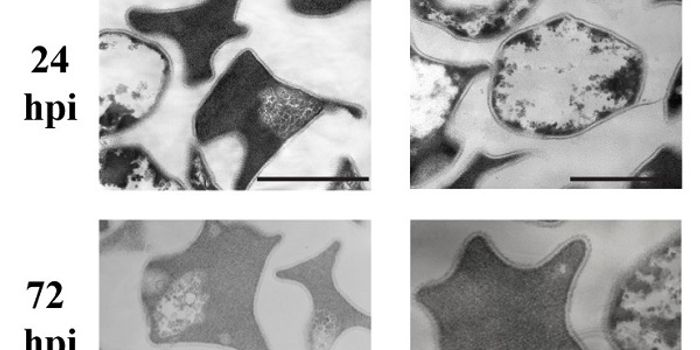

NOV 08, 2015Cell & Molecular BiologyL. monocytogenes is a bacteria that can be found anywhere in nature. It is a psychrotolerant pathogen, meaning, tha ...